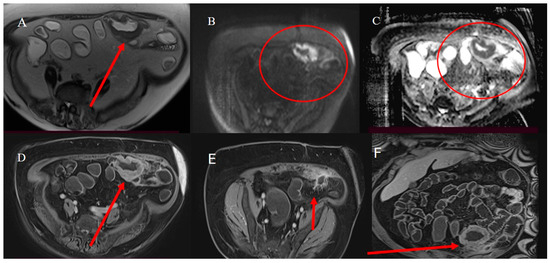

- Masselli, G.; Casciani, E.; Polettini, E.; Laghi, F.; Gualdi, G. Magnetic resonance imaging of small bowel neoplasms. Cancer Imaging 2013, 13, 92–99. [Google Scholar] [CrossRef] [PubMed]

- Faggian, A.; Fracella, M.R.; D’alesio, G.; Alabiso, M.E.; Berritto, D.; Feragalli, B.; Miele, V.; Iasiello, F.; Grassi, R. Small-Bowel Neoplasms: Role of MRI Enteroclysis. Gastroenterol. Res. Pract. 2016, 2016, 9686815. [Google Scholar] [CrossRef]

- Boone, D.; Taylor, S.A. Magnetic Resonance of the Small Bowel: How to Do It. Magn. Reson. Imaging Clin. N. Am. 2019, 28, 17–30. [Google Scholar] [CrossRef] [PubMed]

- Maccioni, F.; Busato, L.; Valenti, A.; Cardaccio, S.; Longhi, A.; Catalano, C. Magnetic resonance imaging of the gastrointestinal tract: Current role, recent advancements and future prospectives. Diagnostics 2023, 13, 2410. [Google Scholar] [CrossRef] [PubMed]

| MRI | ||||

| MRE | For SBT tissue characterization in non-emergency cases or in stable patients | Intestinal distension with oral biphasic contrast agents, with an optimal volume of 1000–1500 mL that can be ingested over 45–60 min before the examination; T2 HASTE with and without FS on axial and coronal plane; Trufi T2 on axial and coronal plane; DWI; VIBE T1 FS pre-contrast on coronal plane; if stenosis is present, it may be helpful to use the cine-balanced sequence | Tissue characterization through multiparametric sequence; DWI can be used to predict and monitor SBTs; DWI is more sensitive to detecting LI metastasis in liver steatosis | Claustrophobia; PMK not MRI-compatible |